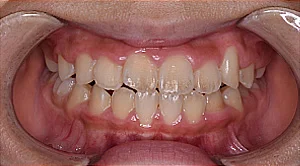

子どもの矯正

成長過程にあるお子さまは、その成長をうまくコントロールして導くことで歯並びと咬み合わせを良くしていくことが大切です。

当院では、お子さまの歯並びが悪い方向に向かっている「原因」は何なのかをきちんと診断し、その改善を図ったうえで、歯並びを整えていく将来を見据えた治療を行なっています。